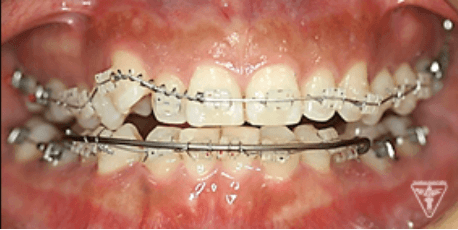

治療過程①